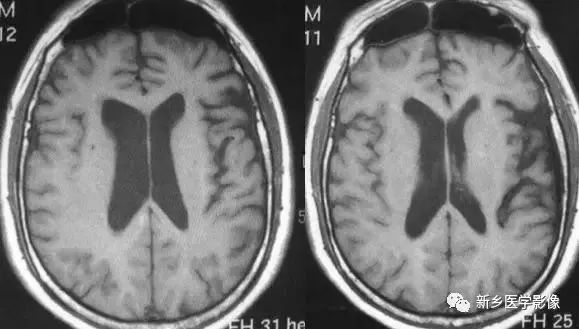

一侧脑室扩大

❶ 正常变异

正常人中,有相当一部分人双侧侧脑室大小不一致、不对称,一侧侧脑室明显大一于另一侧。临床上,智力及精神发育正常,无临床意义。